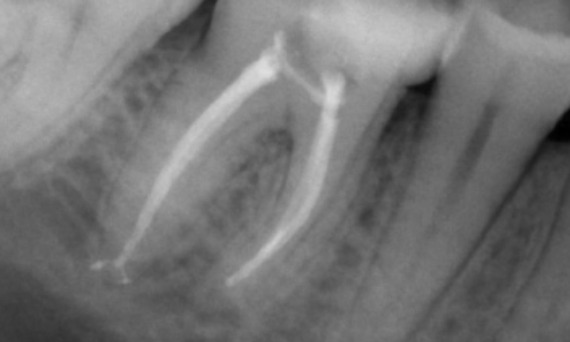

Antes: Radiotransparencia periapical asociada principalmente a la raíz distal y pérdida de la lámina dura en la raíz mesial.

Después: Se eligió TruNatomy en este caso para permitir un mejor abordaje de la caries y enfocarse en la conservación de la dentina pericervical, especialmente en el aspecto mesial, donde el diente presentaba una restauración más menor.

Bath, Reino Unido